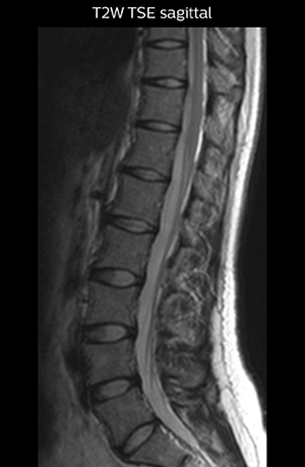

“For example, in sagittal images, when the presence of fat is observed in the intervertebral foramen, it suggests that there is a margin around the nerve. Similarly, the absence of fat indicates that the nerve is being compressed. So, we used to deduce nerve compression indirectly. With NerveVIEW, however, we can observe the condition of the nerves directly, regardless of the presence or absence of fat. We always prefer such direct observation of anatomy over having to make an inference about it.”

“Although symptoms of typical disc herniation and atypical hernia are very similar, the actual site of herniation is different. It is therefore important to characterize the nerve’s condition both inside and outside of the intervertebral foramina. “Conversely, if we see no abnormality in NerveVIEW, we can assume at least that there is no severe condition that requires surgery. Like this, it can help us avoid unnecessary surgery. NerveVIEW can have a tremendous impact in this way.”

Lumbar spine MRI

examination with 3D NerveVIEW

T1W sagittal and axial

3D NerveVIEW

T2W sagittal and axial